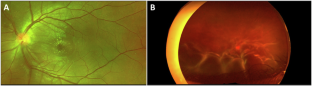

Patients with evidence of active TB were predominantly younger. Typical manifestations of ocular TB (OTB) were more frequently observed in patients with active systemic TB (p < 0.001) and were significantly associated with younger age (p = 0.002). In patients without active systemic TB but positive Mtb PCR from ocular fluid, ocular manifestations closely resembled those of patients with active systemic TB, particularly with respect to the presence of choroidal granulomas. In contrast, patients with an undetermined cause of uveitis who tested positive for IGRA were older, and their clinical features were more often atypical.